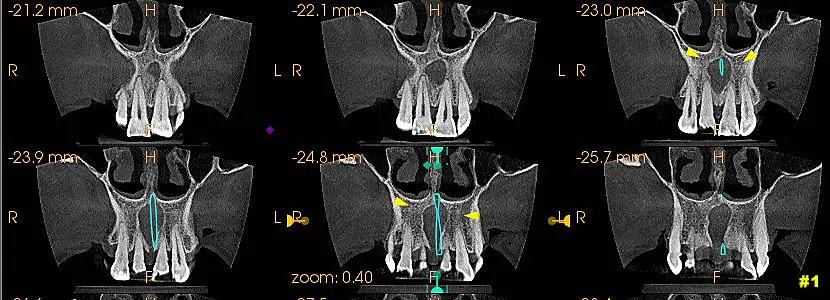

Luego de un control de barrido en la tomografía se observo en zona anterior de maxilar superior ensanchamiento del canal nasopalatino y expansión con forma ovalada de las paredes del conducto. Imagen 1 – 2 y 3.

-Tomografía Cone Beam realizada en octubre 2022 donde se procede a observar la presencia de dicha patología (Quiste Nasopalatino).